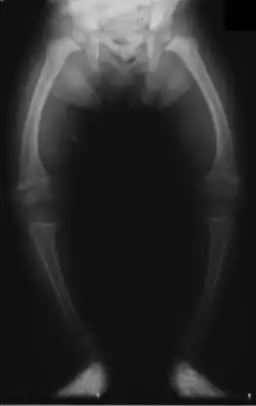

| X-ray of a two-year-old with rickets, with a marked bowing of the femurs and decreased bone density | |

An X-ray or radiograph of an advanced sufferer from rickets tends to present in a classic way: the bowed legs (outward curve of long bone of the legs) and a deformed chest. Changes in the skull also occur causing a distinctive "square headed" appearance known as "caput quadratum".[14] These deformities persist into adult life if not treated. Long-term consequences include permanent curvatures or disfiguration of the long bones, and a curved back.[15]

- Radiography typically show widening of the zones of provisional calcification of the metaphyses secondary to unmineralized osteoid. Cupping, fraying, and splaying of metaphyses typically appears with growth and continued weight bearing.[36] These changes are seen predominantly at sites of rapid growth, including the proximal humerus, distal radius, distal femur and both the proximal and the distal tibia. Therefore, a skeletal survey for rickets can be accomplished with anteroposterior radiographs of the knees, wrists, and ankles.[36]